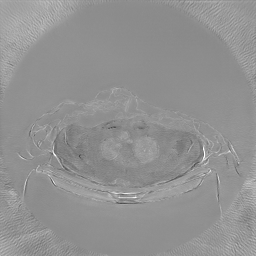

III-C Uncertainty analysis

Classical diffusion models reconstruct images by progressively denoising from an initial Gaussian noise image, a process that inherently introduces uncertainty due to random noise initialization. In contrast, I2SB directly learns a diffusion bridge between two sample distributions, effectively bypassing the need for random noise sampling and thereby reducing reconstruction variability.

To assess the uncertainty of our method, we performed multiple reconstructions using different random seeds. As shown in Fig. 3, the ground truth and representative sampled images are presented in Fig. 3(a) and (b–d), respectively. The mean reconstruction and pixel-wise standard deviation across runs are displayed in Fig. 3(e) and (f). Only minimal differences are observed between reconstructions, indicating that I2SB produces highly consistent results. These findings confirm that, compared with classical diffusion models, I2SB substantially reduces uncertainty across repeated reconstructions.